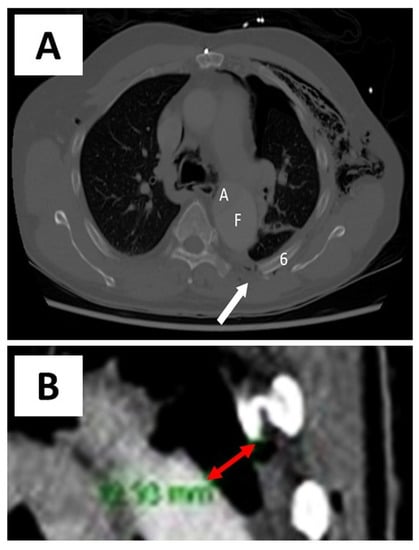

A 66-year-old man presented to the emergency department after being struck by a cyclist. He complained of left-sided chest, shoulder/hip pain, and post-traumatic amnesia. He had a past medical history of hypertension, hypercholesterolaemia, and chronic, residual, Stanford Type A AD, which was repaired in 2014. On examination, he was haemodynamically stable with a brachial blood pressure of 115/71 mmHg, no significant blood pressure differences between arms, a respiratory rate of 22 breaths per minute, and a pulse oximeter saturation of 95% on 2 litres nasal prong oxygen. He had a tender left chest wall posteriorly and laterally, with extensive subcutaneous emphysema over his chest wall and neck bilaterally. He had reduced air entry in his left chest. His had dual heart sounds without murmurs. A computed tomography (CT) scan of his chest showed a comminuted left clavicle fracture, left rib fractures from the second to the ninth, with flail segments from the third to the ninth, and a moderate left pneumothorax (Figure 1 and Figure 2). The sixth posterior rib fracture was only 13 mm away from the aorta (Figure 1 and Figure 3A). The CT also demonstrated that the residual AD had increased in size since the original diagnosis in 2014. A CT of his brain and facial bones showed no new intracranial pathologies or fractures.

Figure 2. Preoperative 3-dimensional CT reconstruction of chest. Preoperative 3-dimensional CT reconstruction of chest—white arrows point to fracture sites.

Figure 3. Chest CT (axial view)—preoperative and 6-week postoperative images. (A). Preoperative chest CT demonstrating the proximity of the sixth rib fracture site to the false lumen of the aorta (~13 mm as marked by the double-tipped red arrow). (B). 6-week postoperative chest CT showing in situ RibFixTM plates.